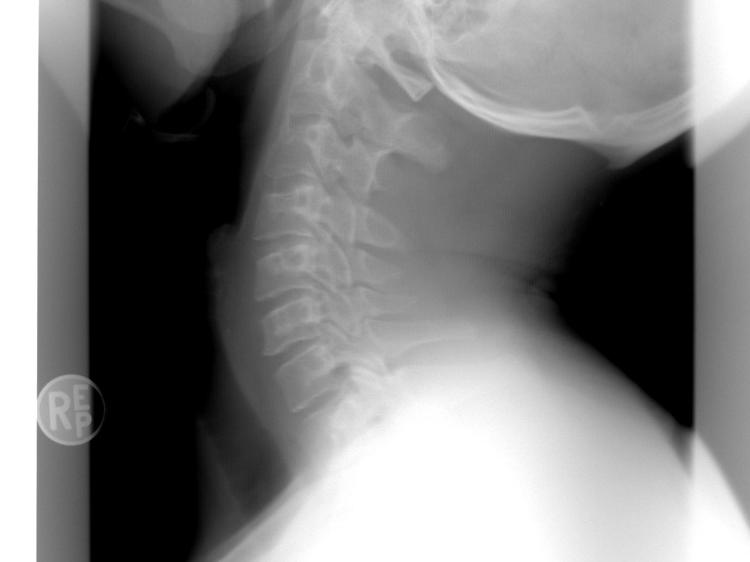

颈椎两侧的横突孔里,藏着一根重要的血管——椎动脉,它专门给脑干、小脑和后脑勺的枕叶供血(这些部位正好管平衡、协调和视觉)。当颈椎开始退变,比如长出骨赘(俗称“骨刺”)或者椎间盘膨出,就可能压迫椎动脉,导致血流不稳定。研究发现,颈椎最上面的C1-C2节段(也就是寰枢椎)因为位置特殊,转头时特别容易受影响,这时局部血流速度可能下降40%。这就是为什么有些人一转头就晕得厉害——血流波动和体位直接相关。

颈部肌肉如果长期紧张痉挛(比如总低头导致的代偿性紧张),会引发一连串问题。比如胸锁乳突肌(脖子前面连接胸骨和锁骨的肌肉)、斜方肌(肩膀到脖子后面的肌肉)一直紧着,不仅会加重对血管的压迫,还会通过颈椎神经反射,影响负责平衡的“前庭核团”功能。这种肌肉力量失衡,会导致平衡差、看东西晃,大概占颈椎性头晕的21%。不过这种表现容易和耳石症等前庭系统本身的疾病搞混,得结合颈椎的影像学检查才能区分开。

医生通常会建议做颈椎动态影像学检查,比如磁共振(MRI)能清楚看到椎动脉的走向、脊髓有没有受压;椎动脉超声造影可以评估血流情况。治疗会根据每个人的情况“定制”——比如牵引(用外力拉颈椎,缓解压迫)、生物反馈(通过仪器帮你感知肌肉紧张度,学会放松),或者运动康复(比如针对性的颈部肌肉训练)。